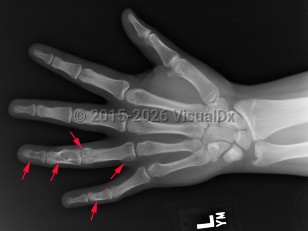

Ollier disease and Maffucci syndrome are nonhereditary conditions that present as multiple enchondromas. Ollier disease involves multiple asymmetric enchondromas of the digits. It is most commonly seen in childhood. These slow-growing tumors usually stop growing after puberty, but masses can create deformity and limb asymmetry. Pathologic fractures may be seen. Ollier disease has a 15%-20% risk for secondary chondrosarcoma.

Solitary enchondroma itself has about a 1% risk of malignant transformation into chondrosarcoma. It is important to distinguish enchondroma from chondrosarcoma, a malignant tumor. Patients with chondrosarcoma of the extremity are more likely to present with nighttime pain, pathologic fracture, endosteal cortical scalloping, bony reactive changes, and larger lesions (> 6 cm). Assume any pelvic cartilage tumor in an adult is a chondrosarcoma until proven otherwise. Rib and scapula lesions are also more likely to be chondrosarcomas.